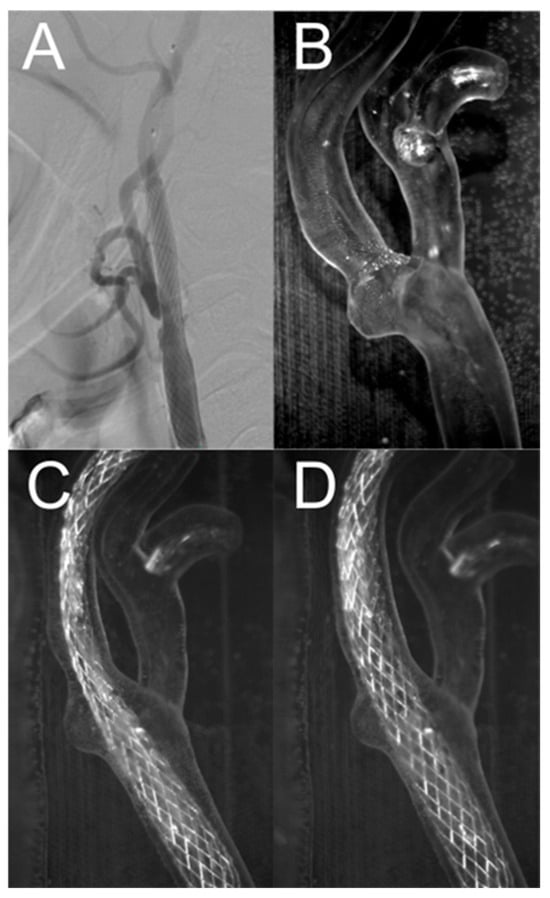

Figure 12A shows a close-up of the CT angiography image of the inserted stent after percutaneous angioplasty. Figure 12B shows a close-up of the artery geometry without a stent. Figure 12C,D show the artery models before and after balloon inflation, respectively. As shown in Figure 12C, the deployed stent did not produce sufficient radial force to restore the nominal lumen of the vessel. After balloon inflation, the vessel lumen was restored, with the stent closely adhering to the model wall, and the artery model visibly straightened, as shown in Figure 12D. The changes in the shape of the vessel and stent were similar to those observed after percutaneous angioplasty performed on a living patient, as shown in Figure 12A.

Figure 12.

Comparison of artery with Carotid WALLSTENT™ after angioplasty with stent placement (A) and carotid artery model (B) with carotid artery stent before (C) and after (D) inflating the balloon.